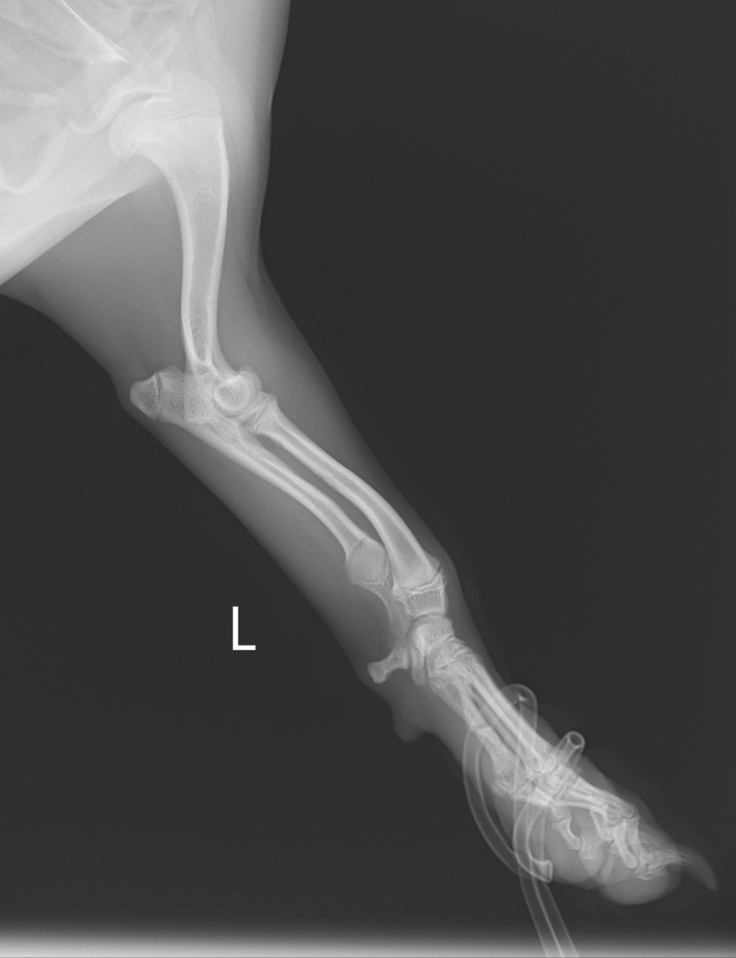

まず、レントゲン所見ではやはり手術適応に入るとのことです。ですがりくの場合は複雑に変形してしまっていて(これもミックス犬のせいだと思われます)、リスクも高い手術で整形専門の病院でやらなければならないことは勿論、やったとしても完全完治にはならないと。

(本来平行にならなければいけない関節が、緑線で曲がっていることが分かります)

(2021.2.11撮影 この時はまだ中等度変形)

尺骨の成長が止まり、橈骨が成長し続けるため弓矢のように曲がってしまっています。